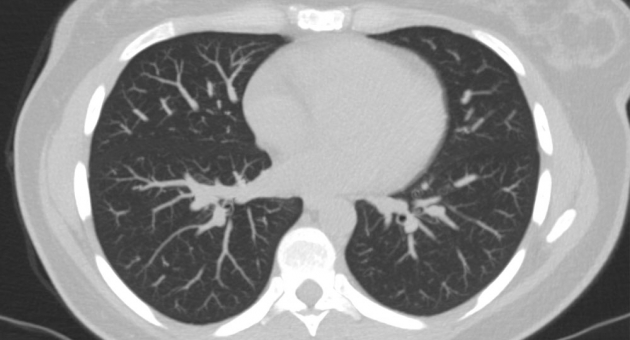

КТ лёгких – отличная уточняющая и детализирующая методика исследований. Она выявит все подробности поражений, проведёт оценку мягких тканей, сосудов, полых органов с получением 3-D картинки. На сегодняшний день компьютерная томография лёгких, проведённая профессионалами на новейшем оборудовании, особенно актуальна в связи с распространением опасного заболевания – коронавирус.

- Применение оборудования для КТ лёгких с высоким качеством изображения.

Высокое качество изображений и высокопрофессиональный персонал позволяют расшифровать результаты КТ и МРТ в течение 30 минут. Пациентам предоставляются бумажные и электронные заключения врачей-диагностов. Заключение окажет неоценимую помощь в создании целостной картины о здоровье человека, а лечащий врач использует эту информацию для назначения квалифицированного лечения.